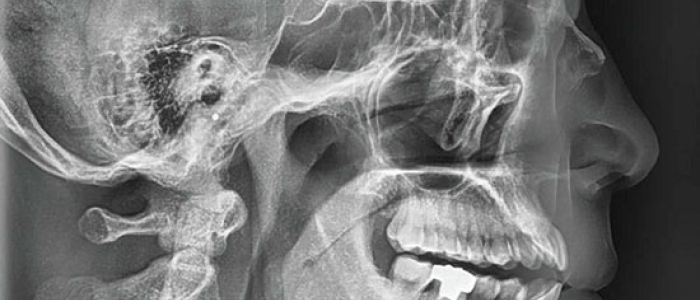

Las radiografías extraorales se emplean cuando no es factible obtener información diagnóstica adecuada en las series de radiografías intraorales, es así que son utilizadas para observar un área grande de los maxilares y del cráneo en una sola radiografía. Los exámenes radiográficos extrabucales tienen el propósito de evaluar áreas grandes del cráneo, dientes impactados y patrones de erupción, crecimiento y desarrollo; examinar la extensión de lesiones grandes, traumatismos, articulación temporomandibular. Son de mucha utilidad principalmente en Ortodoncia y Cirugía Bucal.

Existen varias radiografías extraorales entre las cuales se tiene: